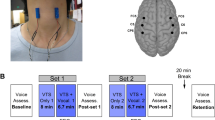

During rest, we observed increased FC in the right medial dorsal premotor cortex (PMd; x | y | z = 24 | −2 | 56; t = 5.26, p = 0.012) within the SMN in PATpre compared to CONTR, increased FC in the left primary auditory cortex (A1; x | y | z = −44 | −14 | 2; t = 5.47, p = 0.004) within the AN in PATpre compared to CONTR and no significant abnormalities in the CEN. We further observed significantly reduced regional homogeneity at the right parieto-temporal junction (TPJ; x | y | z = 60 | −50 | 8; t = 4.97, p = 0.039; Fig. 2) in PATpre compared to CONTR, with a corresponding left-hemispheric trend at k > 50 voxels (x | y | z = −48 | −58 | 14; t = 5.26, k = 86). Post-hoc evaluation of FC changes in these analyses before and after BoNT-A within patients did not yield significant differences.

From left to right: Significant increases (pFWE < 0.017) of long-range FC within the sensorimotor and the auditory network (in red) as well as significant reduction of short-range FC by regional homogeneity (pFWE < 0.05; in blue) overlaid onto the participants’ averaged structural images (clusters displayed at p < 0.001 uncorrected); areas with robust within-group response to tactile stimulation across conditions and participants are underlaid in light green. Slice positions in MNI space in mm are given relative to the anterior commissure (right/anterior/above +; left/posterior/below −). CONTR, healthy controls; PATpre, ADSD patients before botulinum toxin A treatment; L/R, left/right hemisphere.

There was a significant positive association of disease severity by voice handicap index with stimulation-induced activation in the left posterior STG (BA41/42; x | y | z = −52 | −30 | 10; t = 6.01, p = 0.009) caudal to A1 during right face (V1) stimulation in PATpre (Fig. 3). All other regression analyses did not yield significant results.

Left-hemispheric temporal cortices showing spatial pattern of abnormal tactile stimulation-induced changes or abnormal resting connectivity. Clusters with a significant positive relation to symptom severity by VHI during right face (V1) stimulation (in red), are displayed together with primary auditory FC-changes within the auditory network (orange) at rest and left-hemispheric temporal (and parietal) activity changes induced by right-hemispheric tactile stimulation of the face (V1/V2, in yellow/green) at a cluster-forming threshold of p < 0.001 uncorrected.